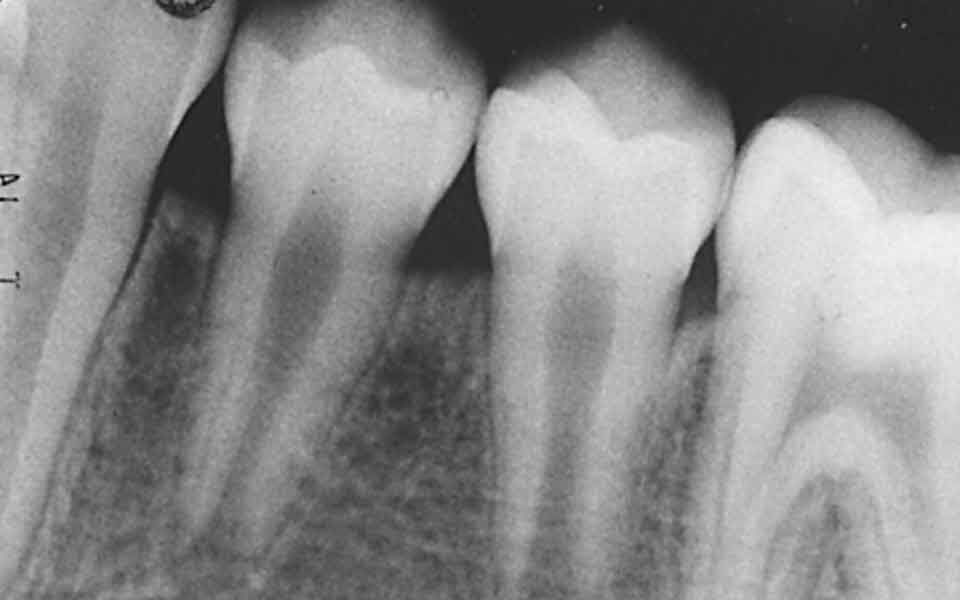

Until recently, our only option when taking a dental X-ray was the exposure of a small film packet, which then took between five and ten minutes to develop. Now, the digital era has brought us an exciting new technology called digital radiography.